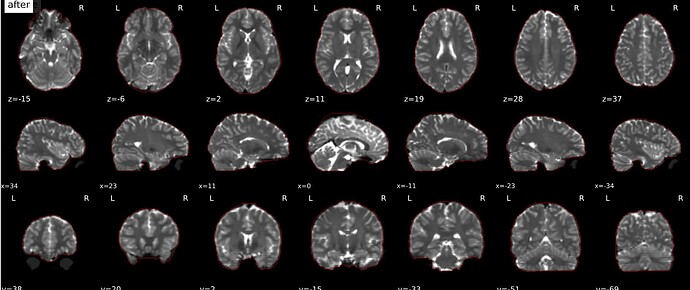

Should the masked (skull-stripped) B0 reference image be used in the alignment of the reference EPI image to the anatomical reference (coregistration)? The gif in the .html output shows a non-masked B0 image (eyeballs can be seen), even though the gif in the B=0 Reference Image step shows good masking. I also do not see the blue and cyan indicators in the b=0 reference gif, nor the red contour in the coregistration gif.